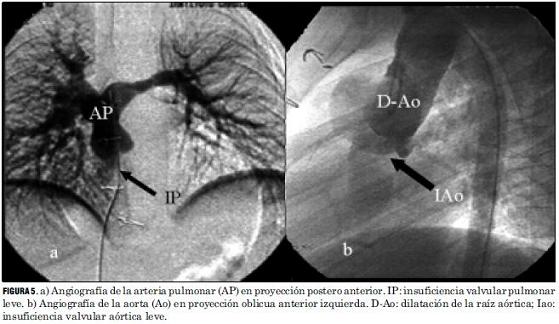

El seguimiento realizado luego del alta hospitalaria a los 60 pacientes ha mostrado que en 48 (77%) la evolución ha sido excelente, con buen crecimiento y desarrollo, permaneciendo en ritmo sinusal, con buena función de ambos ventrículos, sin insuficiencias valvulares ni estenosis supravalvulares significativas, sin requerimiento de procedimientos invasivos adicionales (figura 5).

Las lesiones residuales significativas se presentaron en nueve pacientes (15%). Siete pacientes con estenosis supravalvular pulmonar, uno de ellos asociada a estenosis del origen de la arteria pulmonar rama izquierda, que requirieron angioplastia con balón (figuras 6 y 7), siendo efectiva en cuatro, mientras que en los otros tres requirió cirugía reparadora con la colocación de parche de pericardio bovino. Un paciente presentó una comunicación interauricular residual que debió ser cerrada quirúrgicamente, y otro paciente desarrolló una estenosis subaórtica (figura 8) que se resecó quirúrgicamente, todos con buena evolución (tabla 5).